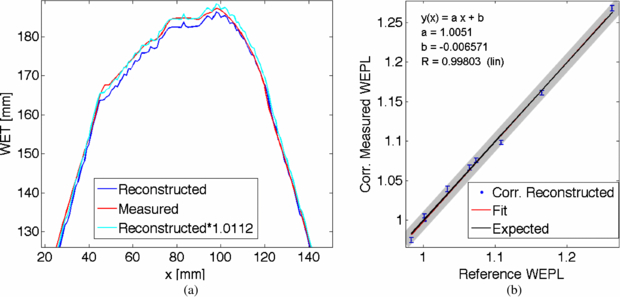

Standard imageThe Ram–Lak filter used in the back projection algorithm is designed to cut-off high frequencies above a set threshold. This filtering process can lead to decreased values in the position space. To account for this, scaling of the obtained data is necessary. In x-ray CT imaging this is performed by applying a linear transformation called Hounsfield scale. Here, for the reconstruction in carbon ion CT, a scaling factor was obtained by comparison of the measured WET values of a single projection with the WET values obtained from the reconstructed image. In figure 12(a) the measured WET distribution for one projection is compared to the calculation from the reconstructed image. Clearly the noise originating from the reconstruction process can be seen. The reconstructed image underestimates the measured values. By multiplication with an estimated correction factor, both distributions agree well. This correction factor was found to be valid for all measured projections and WET distributions. Applying this correction factor to the obtained reconstructed WEPL values (figure 12(b)), the reconstructed and expected WEPL values agree within one standard deviation.

Figure 12. (a) Exemplarily for one projection angle, the measured and reconstructed WET values are plotted. The reconstruction underestimates the WET values by a factor of about 1.0112. (b) The correction factor was used to scale the reconstructed WEPL values. The corrected reconstructed WEPL values were fitted (red). The fit lies on top of the expected values (black). The gray band indicates the standard deviation of the reference WEPL values.

Download figure:

Standard imageThe resolution of the reconstructed WEPL image is given by the standard deviation of the WEPL values shown in figure 12 (vertical bars). The resolvable difference in the WEPL image corresponds to twice the standard deviation given by the fit. The WEPL resolution in the reconstructed carbon ion CT image is better than 0.01 WEPL.

The WET measurement technique with the flat-panel detector was further investigated for sectional tomographic WEPL imaging. The energy scanning technique was slightly modified, so that a PMMA wedge yielded passive energy variation instead of active beam energy variation. This leads to an increased resolution with an energy step size of about 0.3 mm WET. The cylindrical PMMA phantom with Gammex inserts was measured for 80 angles and reconstructed using a filtered backprojection algorithm. The WEPL resolution in the reconstructed carbon ion CT image showed an accuracy better than 0.01 WEPL. The applied dose was not optimized and summed up to in total 8 Gy.